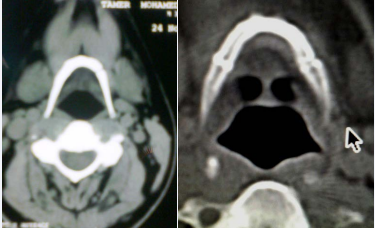

He underwent a CT scan of the neck, which demonstrated a fracture-dislocation between the left greater cornu and body of the hyoid bone Figure.

CT scan showing fracture at the junction of the left greater cornu and body of the hyoid bone.

Figure 1: CT scan showing fracture at the junction of the left greater cornu and body of the hyoid bone.